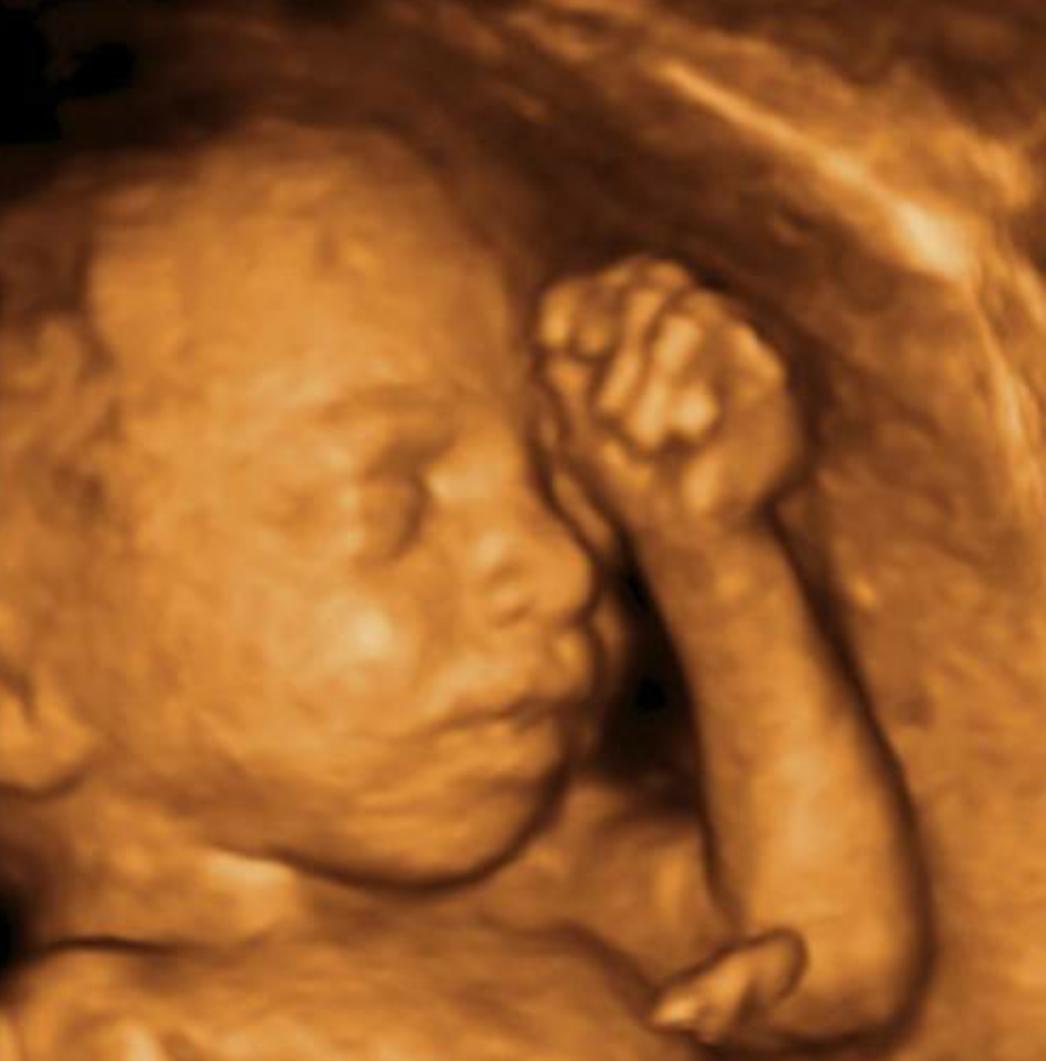

科学解释:孕晚期肚子硬为假宫缩。孕晚期肚子硬,科学的解释就是假宫缩,因为子宫到了孕晚期变得越来越敏感了,受到一些刺激就会引起宫缩,这类宫缩与产前的宫缩不同,胎儿不会因此提早分娩,但是对于这些假性宫缩准妈妈也应该有所注意,当肚子发硬之后,应该立刻停下手中的工作休息一下,如果是在路上发生假性宫缩,就停下脚步,待缓解之后再继续前行。

部分准妈妈会在孕中期感受到频率不高的假性宫缩,愈靠近怀孕后期,频率会愈高,这种宫缩就像是产前子宫的练习,频率不规则,无周期性,不会痛,准妈妈本身不会感到不舒服,通常这种宫缩是会自动消失的。

一般来说,孕晚期肚子硬很有可能是宫缩导致的,这属于正常现象,但是并不是说孕晚期肚子硬就完全没有危险。孕28~37周,如果每10分钟内有2~3次宫缩,持续30秒以上,或伴有阴道血性分泌物排出,即为先兆早产,需去医院检查观察。孕37周以上,感觉有规律的肚子发硬,而且这种情况反复出现,很可能意味着真正的阵痛即将来临。